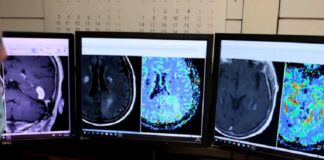

Cáncer de próstata: el Instituto Alexander Fleming suma inteligencia artificial para...

Con 30 años de trayectoria en el tratamiento integral de patologías oncológicas, el Instituto de medicina privada avanza en la detección precoz de esta...